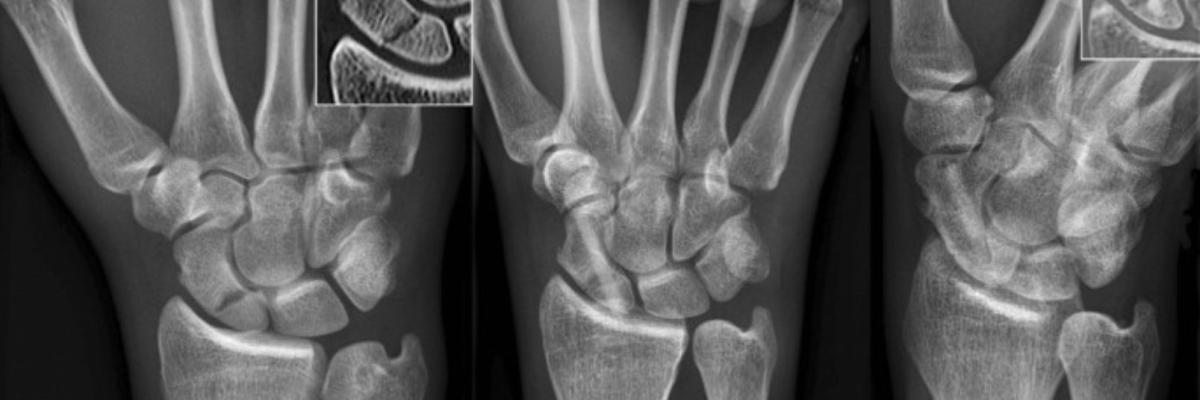

La fractura de escafoides es una de las lesiones óseas más frecuentes de la muñeca, especialmente en caídas con la mano extendida. Aunque su tratamiento inicial suele ser inmovilización o cirugía, el éxito de la recuperación depende en gran parte del trabajo de fisioterapia posterior, que permite recuperar la movilidad, la fuerza y la funcionalidad de la mano. En FisioClinics Logroño, guiamos a nuestros pacientes a través de una recuperación funcional completa tras fractura de escafoides, con ejercicios y técnicas específicas para volver a la vida diaria o deportiva sin secuelas.

El escafoides es un pequeño hueso situado en el lado radial de la muñeca, fundamental para la estabilidad y movilidad de la articulación. Su fractura suele producirse por:

Esta fractura tiene una mala vascularización, lo que puede dificultar la consolidación y alargar la recuperación si no se trata adecuadamente.